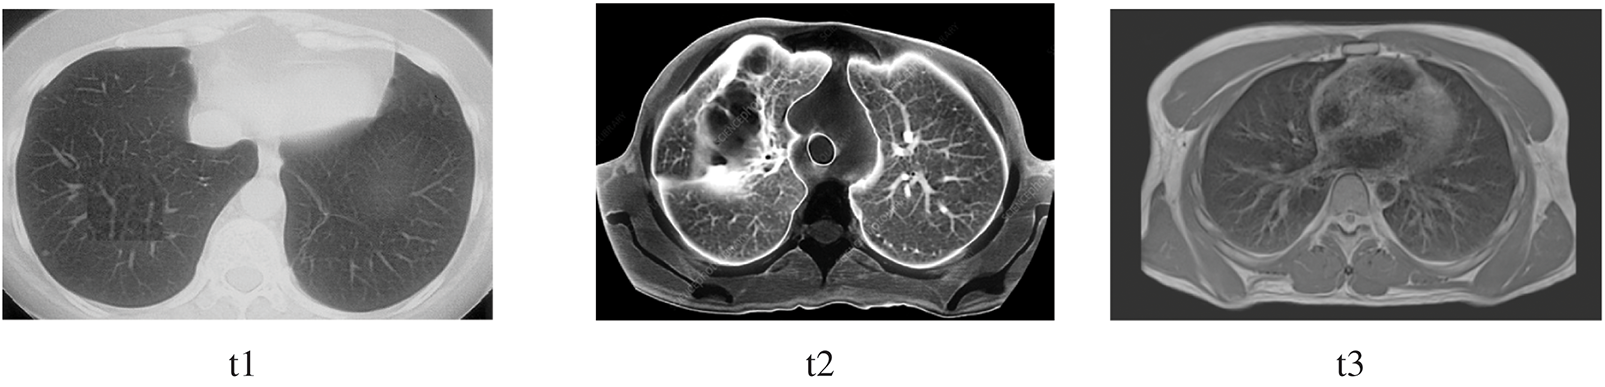

The image has several qualities: intensity, contrast, noise, and darkness. The mathematical illustrations are applied to derive the mean, standard deviation, entropy, skewness, and kurtosis. The precise range for these statistical parameters can sometimes be determined. Nevertheless, for the sake of coherence, there should be significant variation among the numbers, as seen in Table 3. Except for a few factors, all of the properties are consistent across all three images. Controlling darkness may increase contrast, but this cannot overcome certain limitations.

Consequently, certain anomalies occur in the preprocessing stage but can be resolved after segmentation. The correctness of the ground truth is the primary focus since it reveals the segmentation’s precision, homogeneity, and segmented area. The first indication that the segmentation result was excellent is that the homogeneity was more than 90%, as was the ground truth accuracy. Consequently, threshold segmentation achieves higher categorization, uniformity, and accuracy relative to the ground truth.